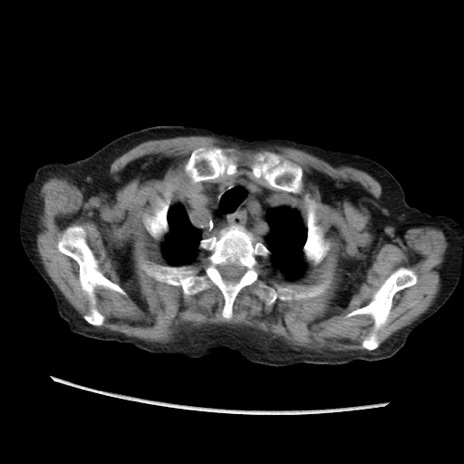

症例31(横断像)

【症例】80歳代 女性

【主訴】腹部膨満感

【現病歴】他院にて肝硬変にてフォロー中。1週間前から便秘、腹部膨満感、臍部腫瘤あり受診となる。

【既往歴】肝硬変

【身体所見】腹部膨隆あり、皮膚変化なし、疼痛なし。

【データ】WBC 4600、CRP 0.25